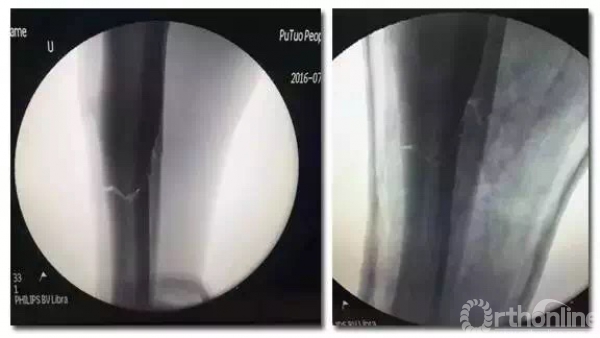

正常术前准备后,手术在透视下按计划顺利进行。术中扩髓11.5mm, 使用直径10mm、长度400mm髓内钉进行内固定。由于腓骨没有移位,腓骨切开固定后有可能延长胫骨愈合时间,基于这方面担心,专家团队决定不对腓骨进行固定。为将对肌肉的刺激降到最小,专家们使用近端螺钉埋头技术,接近完美的使钉头尽可能与皮质水平。

不顾X光射线对自身的影响,专家们术中反复透视,确定螺钉位置及长短,做到每根螺钉固定都恰到好处。手术顺利,完全按照专家团队预期计划进行,结果满意,术后石膏托固定。

X光片示:固定位置好,骨折线几乎看不到。